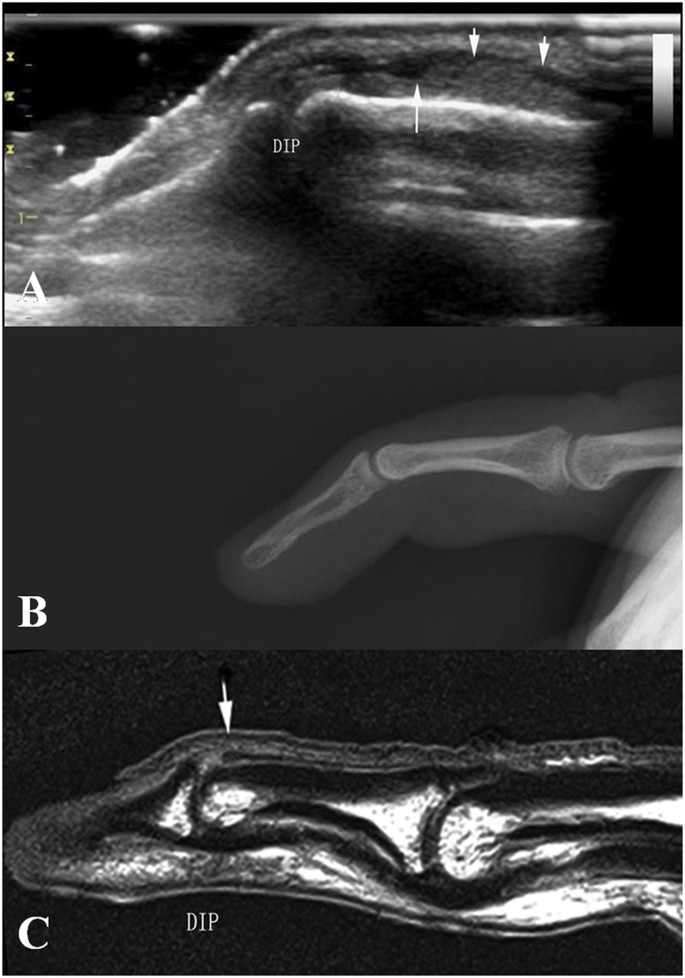

According to ultrasonography findings of the present study, we divided acute closed mallet finger injury into three subtypes: Type A, avulsion fracture without extensor tendon rupture. The ultrasonography showed hyperechoic fracture fragments of the distal phalangeal base and the thicker extensor tendon due to shortening, with the hyperechoic fracture fragments at the distal margin. (Fig. 2); no real-time gliding of the extensor tendon was found during either active or passive movements of the DIP. Type B, complete tendon rupture without fracture. Longitudinal evaluation showed, in Fig. 3, the disruption of the extensor tendon at the level of DIPs with retraction of the proximal tendon stump but no fracture fragments of the distal phalangeal base; no real-time gliding of the extensor tendon during either active or passive movements of the DIP was found. Type C, contusion of extensor tendons. The ultrasonography showed the thicker and hypoechoic extensor tendon which was still integrate in longitudinal plane (Fig. 4). Real-time gliding of the extensor tendon during both active and passive movements of the DIP could be found. The homogeneity for the classifications was high between two radiologists (κ = 0.948).

Type B mallet finger injury. High frequency ultrasonography, X-ray and MRI images of type B mallet finger. Figure 3A: The retracted extensor tendon (short arrow), the distal end of extensor tendon (long arrow); Fig. 3B: X-ray image of mallet finger injury. Figure 3C: the retracted extensor tendon (arrow).

In evaluating the extensor tendon injury, most findings of MRI examination were in line with that of the ultrasonography. For example, in type A and B, longitudinal MRI images showed retraction of the extensor tendon as clearly as ultrasonography. Same in type C, MRI images showed as clearly as ultrasonography that although the injured extensor tendon was thicker and had lower signals on T1-weighted images when compared with the contralateral healthy one, while in longitudinal plane, its integrity was still continuous. In the same time, X-ray could not show the extensor tendon clearly. Significant difference was found among all three examinations (p < 0.05), with even highest significance when taken separately, ultrasonography and X-ray, MRI and X-ray respectively (p < 0.017). We found no significant difference between ultrasonography and MRI (p = 0.613, 0.803, p > 0.017).

For assessing avulsion fracture of the distal phalangeal base, most findings of the ultrasonography results were in line with the X-ray findings in type A. Fracture fragment could be clearly shown as a hyperechoic or hyperintense fragment with good contrast. However MRI was not able to demonstrate the fracture fragment clearly in most cases of this study. Significant difference was found among all three examinations (p < 0.05), with even highest significance when taken separately, ultrasonography and MRI, X-ray and MRI (p < 0.017) respectively. We found no significant difference between ultrasonography and X-ray examination (p = 0.903, 0.903, p > 0.017).